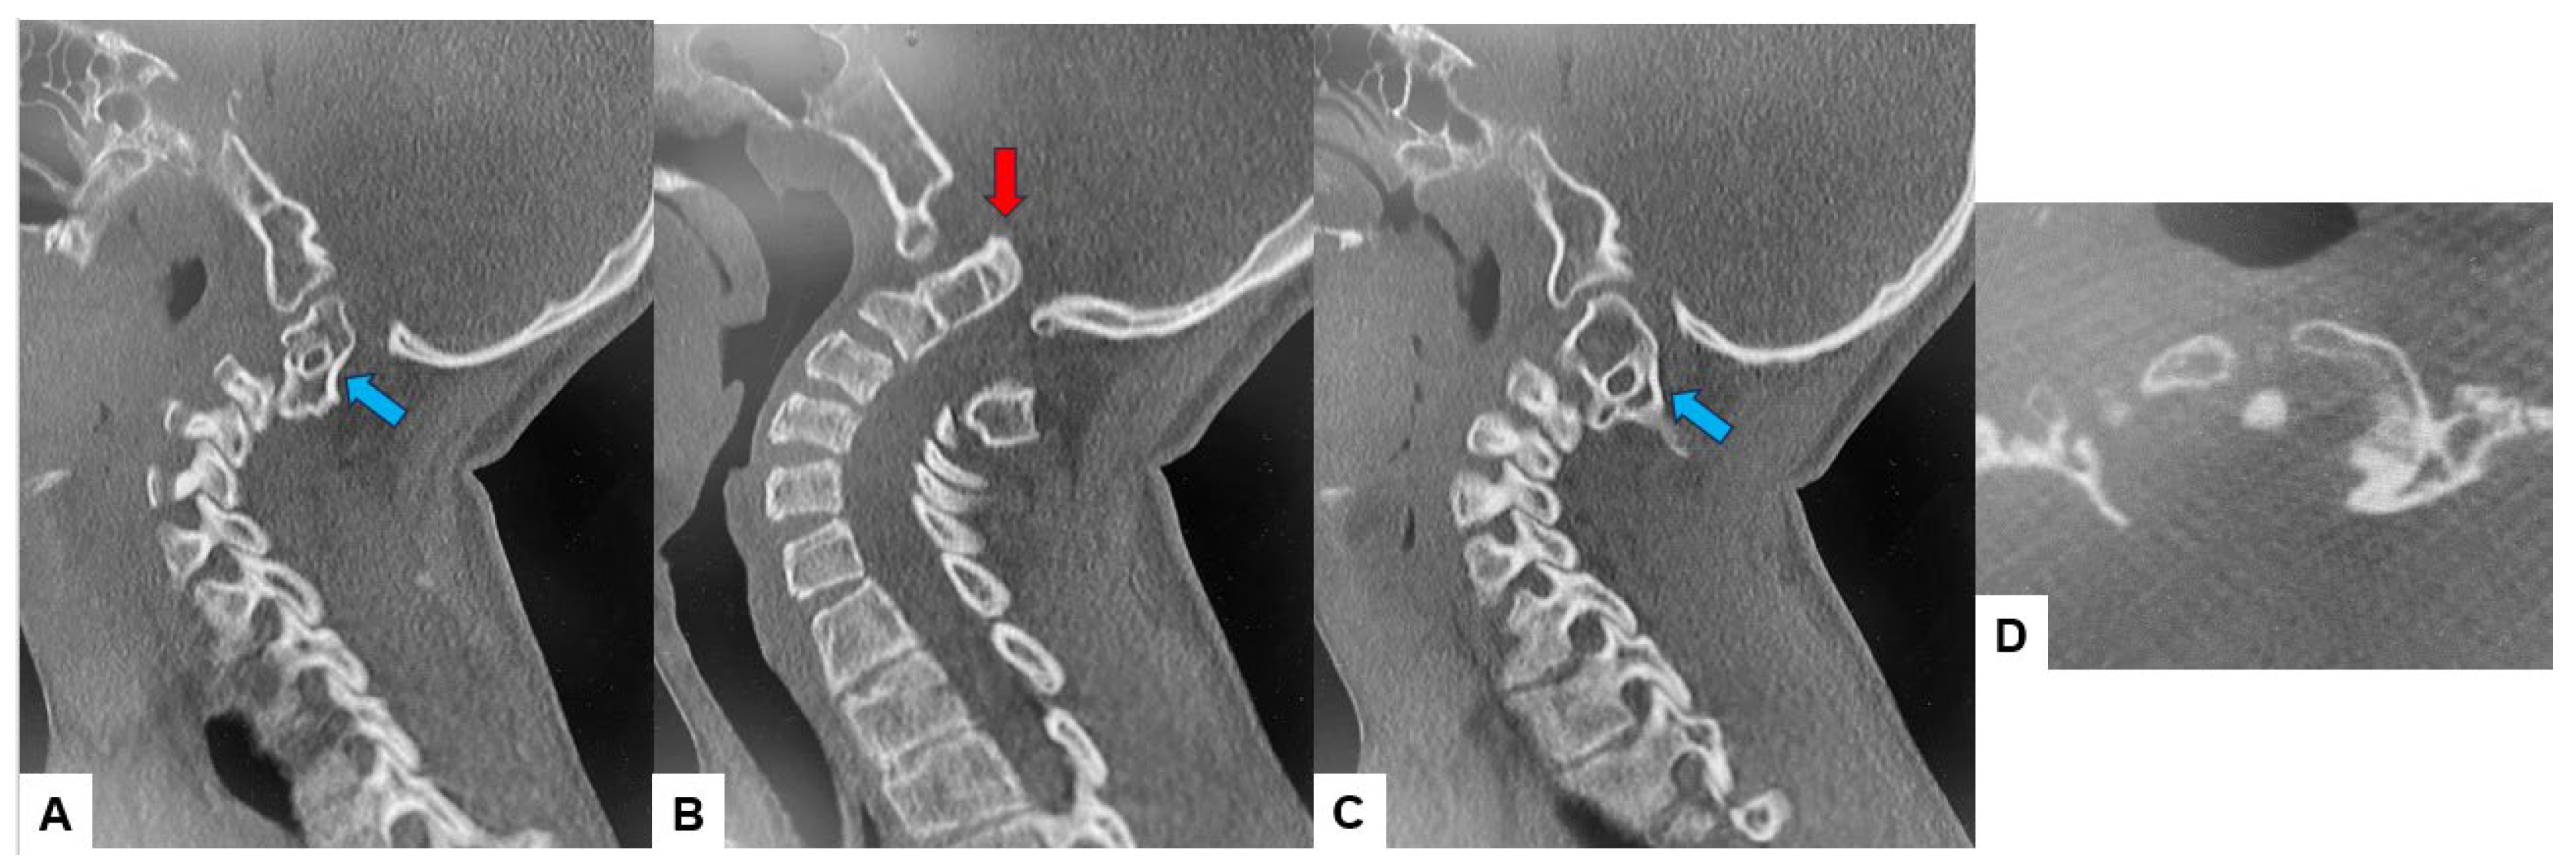

2.3. Preoperative Imaging

2.4. Surgery